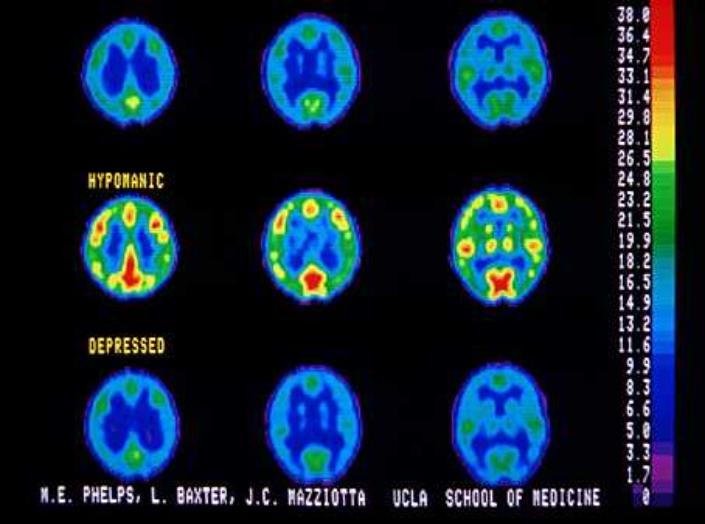

Neuroimaging And Mental Illness - NIMH

2 schizophrenia, or bipolar disorder. Brain imaging scans, also called neuroimaging scans, are being used more and more to help detect and diagnose a number of medical disorders and illnesses. ... Fetch Doc